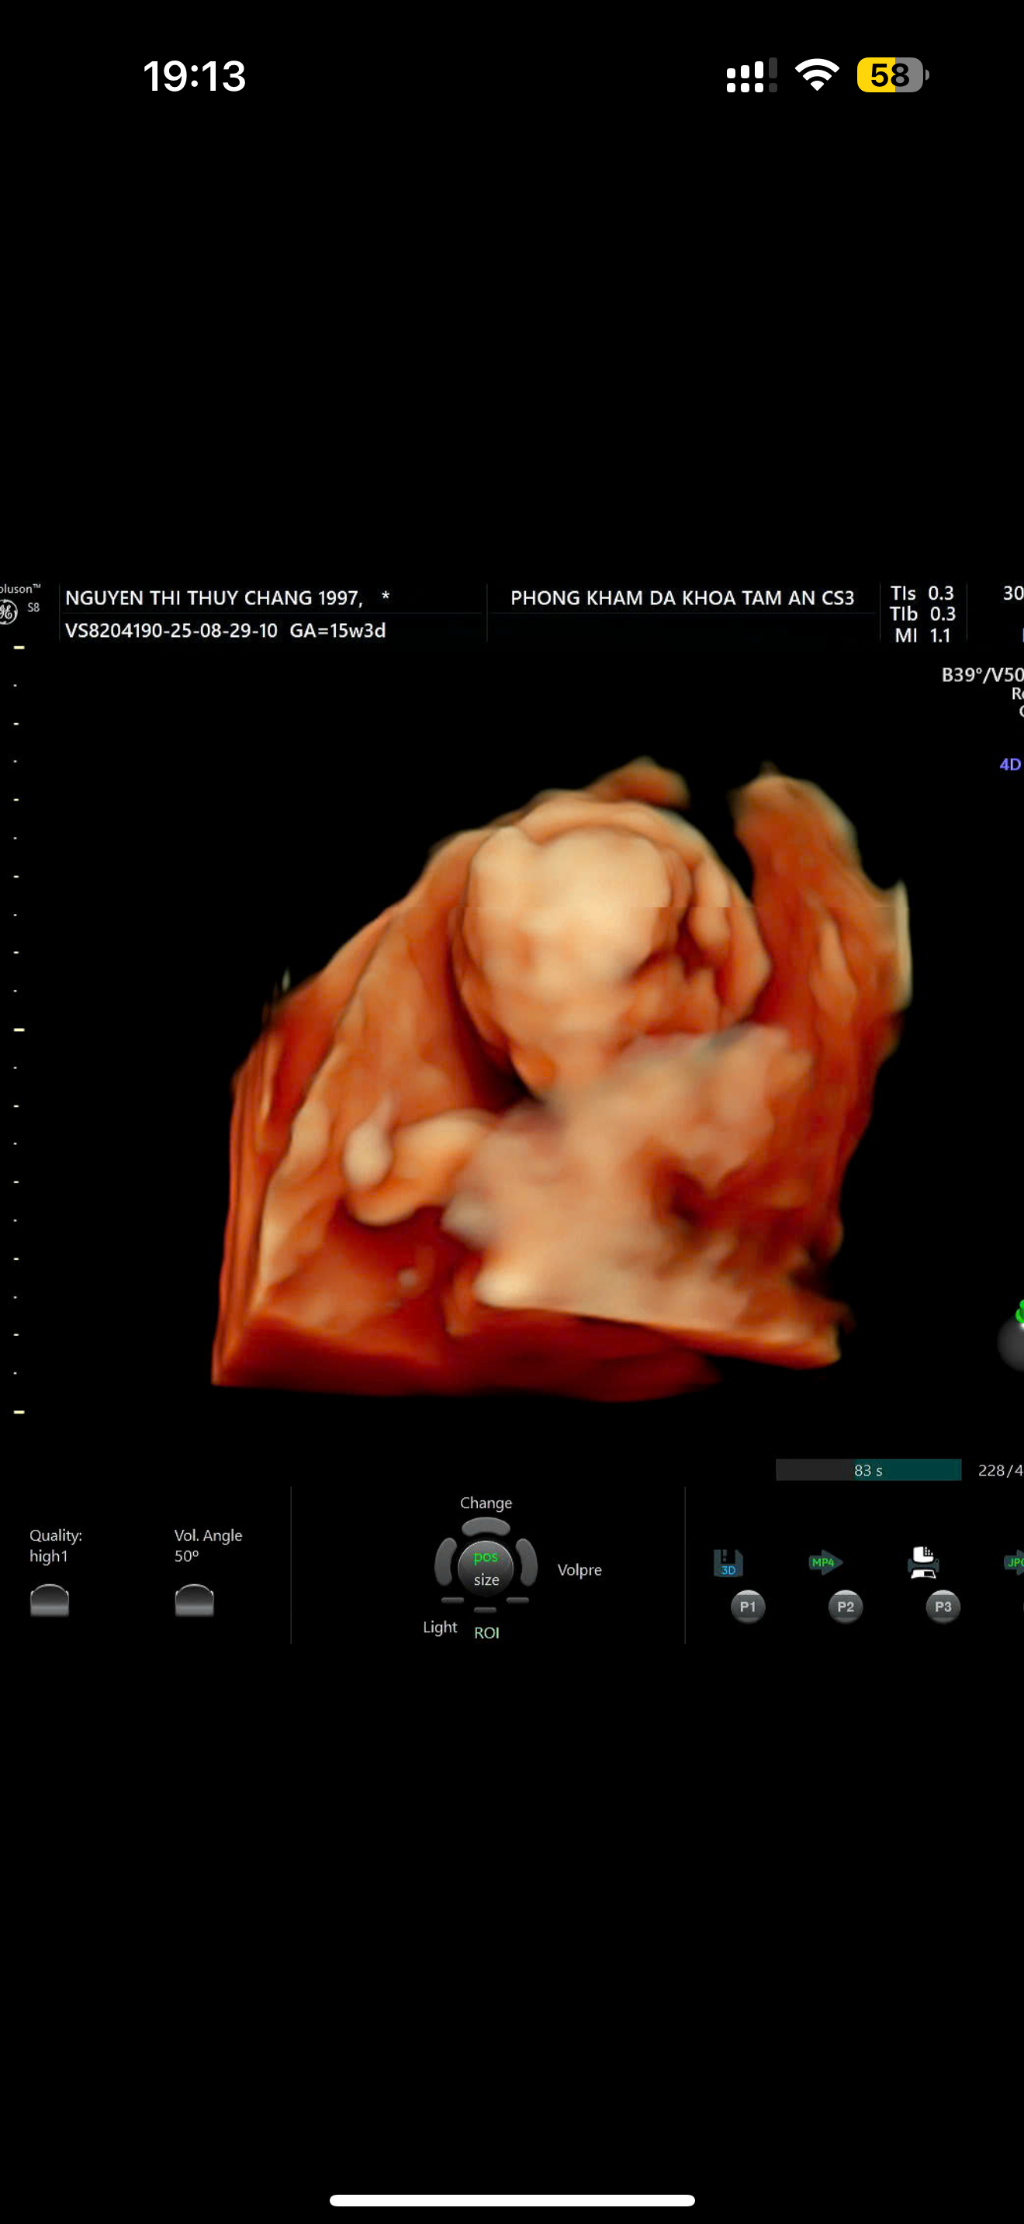

Nguyễn Thị Thùy Chang